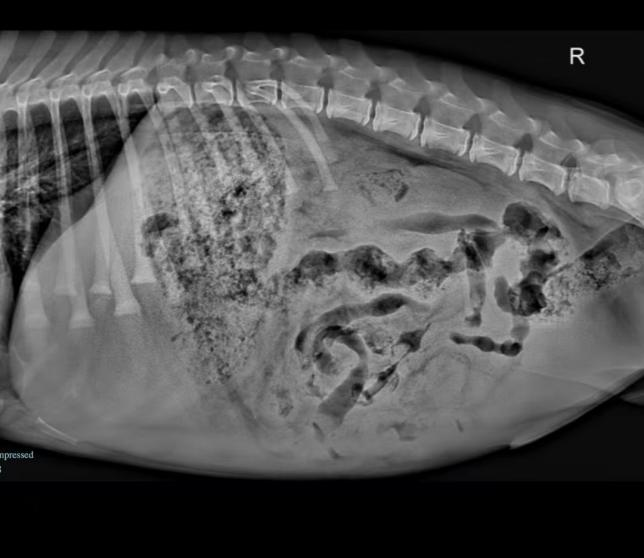

症状描述这只小金毛最近开始出现呕吐和食欲下降的症状,原本活泼的它突然显得非常疲惫,主人看到它精神萎靡不振,十分担心。几天后,金毛的精神状态更加恶化,体力明显下降,犬主赶紧带它来医院就诊。初诊情况来到医院时,这只小金毛显得非常虚弱,精神状态萎靡,且有明显的脱…